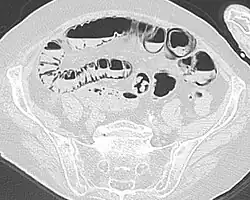

Als Pneumatosis intestinalis (auch Pneumatosis intestinis) wird in der Medizin ein seltenes Krankheitsbild oder in der Radiologie ein seltener Befund bezeichnet. Das Krankheitsbild ist durch eine Gasansammlung in der Wand (intramural) des Verdauungstrakts gekennzeichnet. Die Gasansammlung kann in verschiedenen Schichten der Verdauungsorgane vorkommen. Es wird eine subseröse (unterhalb der Serosa) von einer submukösen (unterhalb der Mukosa) Pneumatosis intestinalis unterschieden. Außerdem kann eine Einteilung nach betroffenem Organ erfolgen, beispielsweise wird die intramurale Gasansammlung im Dickdarm (Colon) als Pneumatosis coli bezeichnet. Eine Sonderform ist die Pneumatosis cystoides intestinalis.

Die Diagnose wird mit Hilfe von bildgebenden Verfahren gestellt. Ausgeprägte intramurale Gasansammlungen können bereits mit einer konventionellen Röntgenaufnahme des Unterleibs (Abdomenübersicht) diagnostiziert werden. Bei geringgradig ausgeprägten intramuralen Gasansammlungen oder wenn die Aussagekraft der Aufnahme beispielsweise durch Blähsucht (Meteorismus) vermindert ist, kann der Befund falsch positiv ausfallen. Die diagnostische Methode der Wahl ist inzwischen die Computertomographie, bei der in der Regel eine sichere Abgrenzung von intramuraler und extramuraler (außerhalb der Wände) Gasansammlung gelingt.